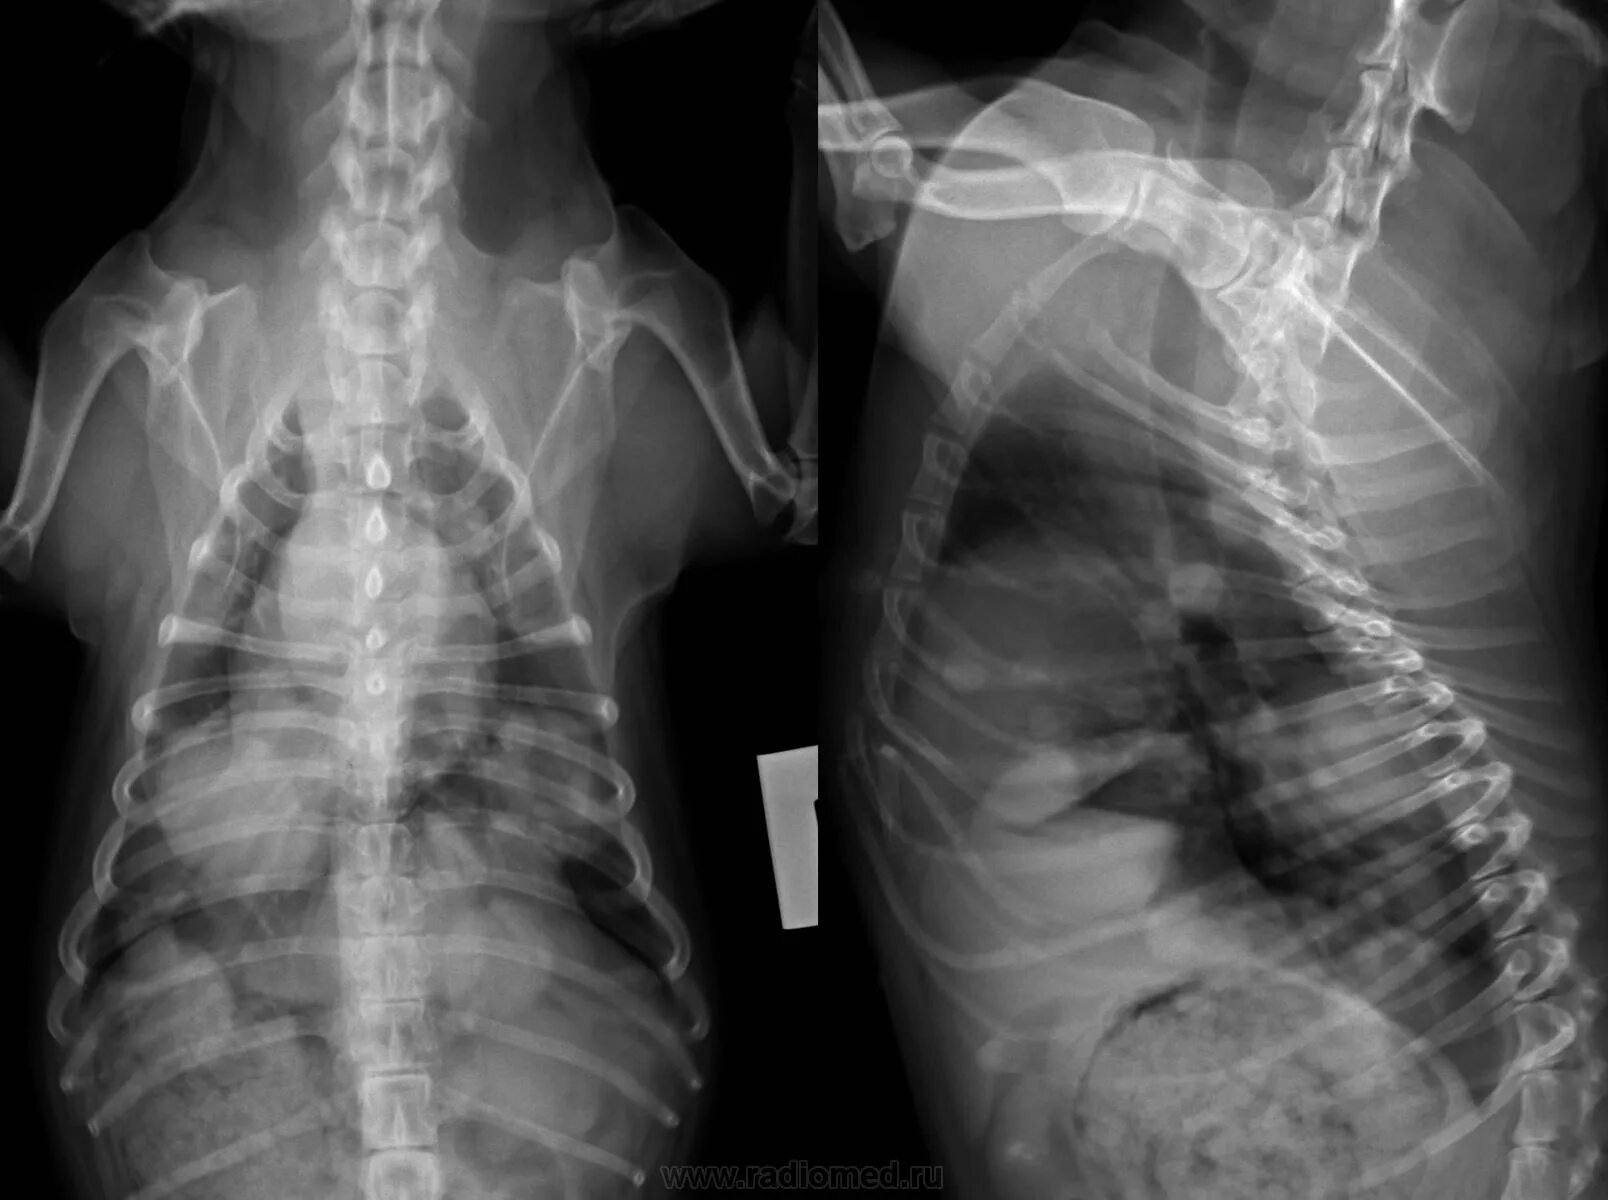

Метастазы в легких что это